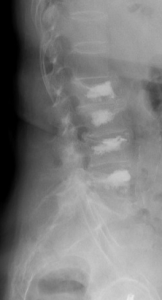

Kyphose

Eine Kyphose ist eine über das normale Maß hinausreichende Ausbildung eines „Buckels“ der Wirbelsäule. Man unterscheidet vor allem drei Erscheinungsformen:

Die Adoleszentenkyphose (Morbus Scheuermann) ist definiert durch eine Deformierung von mehr als drei Wirbelkörpern im Bereich der Brust- und Lendenwirbelsäule mit Keilform der Wirbelkörper, Verschmälerung des Bandscheibenfaches und Irregularität der Wirbelkörperendplatten (sog. Schmorl`sche Knötchen).

Die kongenitale Kyphose ist eine kurzbogige Deformität der thorakalen bzw. thorako-lumbalen Wirbelsäule aufgrund von angeborenen strukturellen Defekten und häufig assoziiert mit Fehlbildungen anderer Organsysteme.